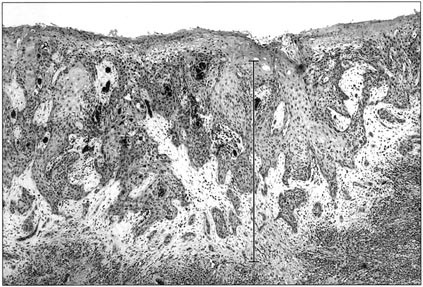

FIGURE 4 | Modern Pathology